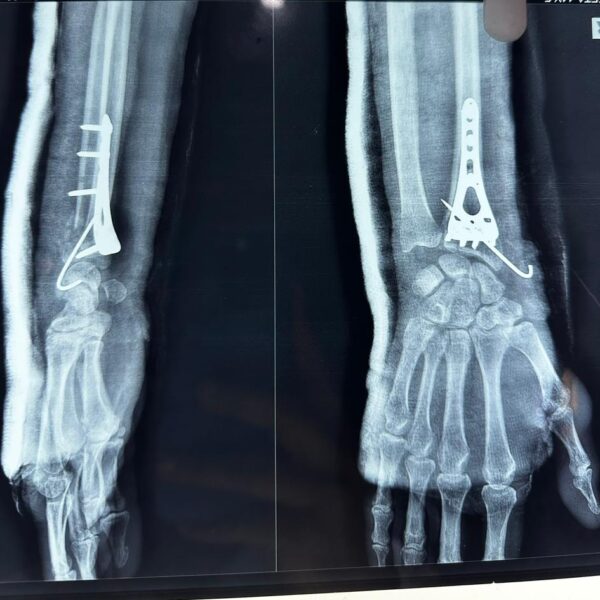

Moments That Mark Meaningful Recovery

Witness real patient transformations at The Ortho Clinic through images that reflect successful treatments and restored mobility.